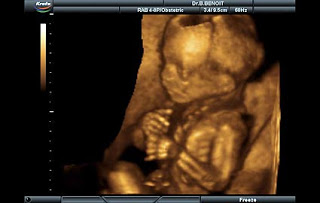

10 haftalık bebek artık rahim içerisinde amnion sıvısı içinde

hareket etmeye başlar, ancak anne henüz hareketlerini hissedemez. Uultrason ile hareketler

görülebilir. El ve ayak eklemleri, diz, dirsek, parmaklar oldukça şekillenmiştir.

Henüz bu kadar erken haftada bile bebek eline dokunan bir cismi tutma refleksini edinmiştir.

Dış kulak ve üst dudak şekillenmiştir. Bu haftada gerçekleşen en ilgi çekici olaylardan

birisi bebeğin kuyruk kısmının düzleşerek görünmez hale gelmesidir. Bebek nefes alıp verme

hareketleri yapar, bunu hava ile değil, amnion suyu yutarak yapar ve ilk defa idrar yapmaya

başlar. (Linkten alıntı)

Demek ki varlık, ALÂKA (rahme yapışkan şey) durumundan 10. haftaya girince kurtuluyor.